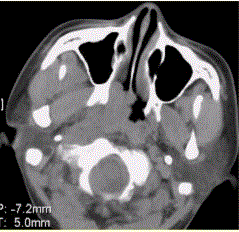

问题 患者男,45岁,鼻塞、涕中带血2周。查体颈部淋巴结增大。专科检查发现,鼻咽腔黏膜肿胀,左侧咽隐窝消失。CT表现如下图。 为明确病变范围和病期,下一步应选择的影像学检查为

选项 A.X线平片 B.CT C.MRI D.DSA E.鼻咽活检 F.鼻咽录像

答案 C